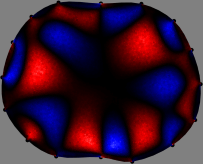

To explain the FER method, we closely examine the correlations among column vectors of the sensitivity matrix 𝕊𝕊\mathbb{S}, described in Fig. 2. The correlation between 𝐒ksubscript𝐒𝑘{\bf S}_{k} and 𝐒subscript𝐒{\bf S}_{\ell} can be expressed as

for i=1,,16𝑖116i=1,\cdots,16[23]. This shows that the column vector 𝐒ksubscript𝐒𝑘{\bf S}_{k} is like an EEG (electroencephalography) data induced by dipole sources with directions uj,j=1,,16formulae-sequencesubscript𝑢𝑗𝑗116\nabla u_{j},j=1,\cdots,16 at locations ΔksubscriptΔ𝑘\Delta_{k}. Given that two dipole sources at distant locations produce mutually independent data, the correlation between 𝐒ksubscript𝐒𝑘\mathbf{S}_{k} and 𝐒subscript𝐒\mathbf{S}_{\ell} decreases with the distance between ΔksubscriptΔ𝑘\Delta_{k} and ΔsubscriptΔ\Delta_{\ell}. Fig. 2 shows a few images of the correlation 𝐒k,𝐒(|𝐒k||𝐒|)1subscript𝐒𝑘subscript𝐒superscriptsubscript𝐒𝑘subscript𝐒1\left\langle\mathbf{S}_{k},\mathbf{S}_{\ell}\right\rangle(|\mathbf{S}_{k}||\mathbf{S}_{\ell}|)^{-1} as a function of \ell for four different positions ΔksubscriptΔ𝑘\Delta_{k}. The correlation decreases rapidly as the distance increases. In the green regions where the correlation is almost zero, 𝐒subscript𝐒{\bf S}_{\ell} is nearly orthogonal to 𝐒ksubscript𝐒𝑘{\bf S}_{k}.